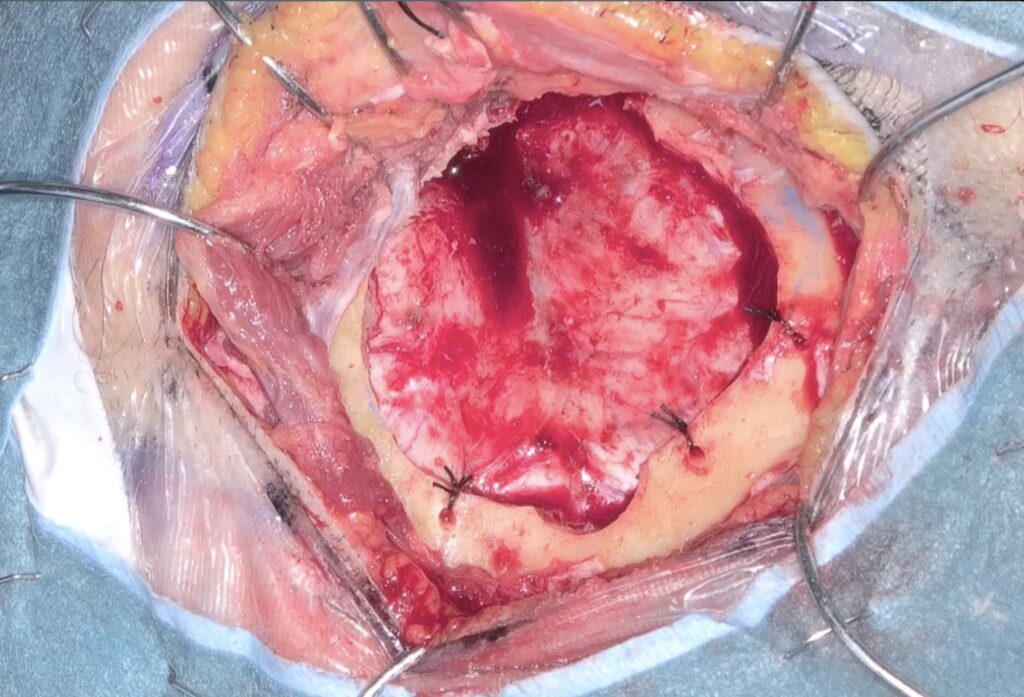

59歳女性の右中大脳動脈瘤を鍵穴クリッピングをしました。後遺症なしでした。 2025 12/12 脳動脈瘤・鍵穴 2025年12月12日13年前にくも膜下出血を起こしunknown SAHと診断され経過を見てきた患者さんに動脈瘤が徐々に育ってきたケースです。鍵穴クリップで対処しました。ScreenshotScreenshotScreenshotScreenshotScreenshotScreenshotScreenshotScreenshot 脳動脈瘤・鍵穴 よかったらシェアしてね! URLをコピーしました! URLをコピーしました! 251024金 橋本信夫先生に久しぶりにお会いしました。 251029水 第84回日本脳神経外科総会(パシフィコ横浜)初日 この記事を書いた人 kikuta 関連記事 未破裂中大脳動脈瘤の鍵穴クリッピング術を行いました。後遺症を認めませんでした。 2026年4月27日 2026年2月 52歳女性 左内頸動脈-眼動脈分岐部動脈瘤クリッピング術を行いました。 2026年3月21日 56歳女性 内頸動脈眼動脈分岐部動脈瘤クリッピング術をしました。軽度視野欠損が出ましたが無事退院されました。 2026年2月19日 63歳男性、右内頸動脈瘤開頭クリッピング術 2026年1月6日 58歳男性 中大脳動脈瘤を鍵穴クリップしました。合併症なく退院されました。 2025年12月17日 44歳女性 SAH PICA遠位部動脈瘤クリッピングを指導しました。 2025年12月17日 2025年5月 68歳女性未破裂Acom 動脈瘤6.6mmのクリッピング術 2025年9月26日 前交通動脈瘤をクリッピングしました 2025年2月26日